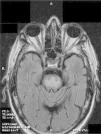

Síndrome confusional en paciente con hiponatremia severa